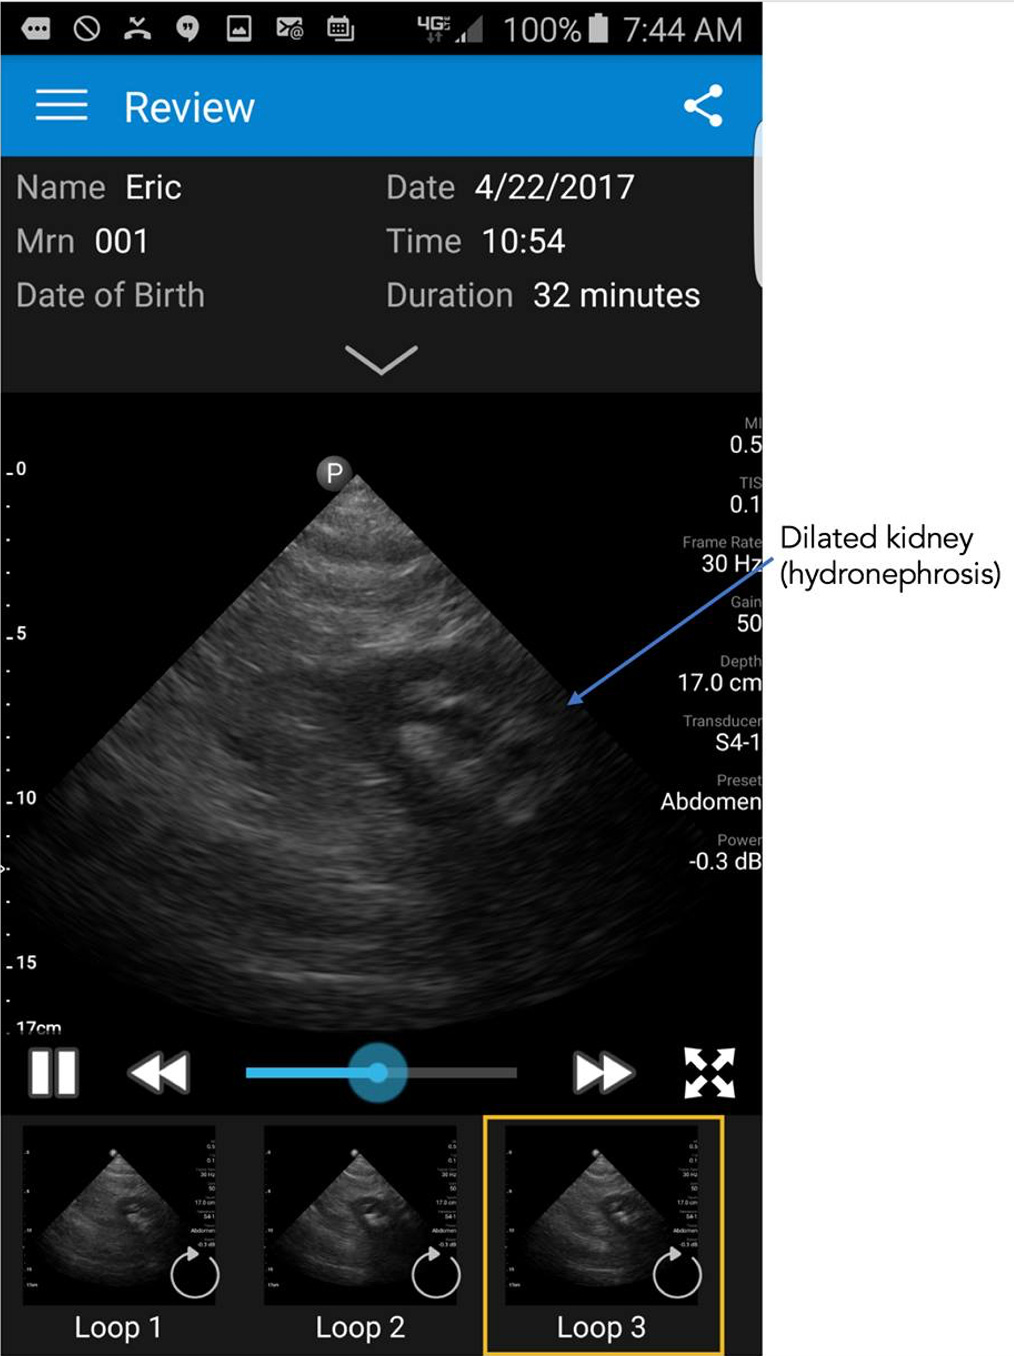

Ironically, months after that medical selfie I had abdominal pain that was severe and something I had not experienced before. So I got out the the smartphone ultrasound probe to image my abdomen and found that I had a dilated left kidney as seen below. Which led me to believe I had a kidney stone and was suffering from renal colic.

You can just imagine the reaction of the emergency department physician when I presented and said I have abdominal pain and a dilated left kidney, “do you want to see it?” Nonetheless, he sent me for a CT scan which showed similar dilation of the kidney and localized the stone.